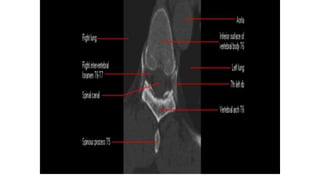

Thoracic spine

X-ray in AP and Lateral

projections.

Vertebral body (star ) of

T12 with rib hypoplasia;

T10–T11 intervertebral

foramina (circle ); T11

right pedicle(arrowhead )

Thoracic spine X-ray inAP and Lateral projections. Vertebral body (star ) of T12 with rib hypoplasia; T10–T11 intervertebral foramina (circle ); T11 right pedicle(arrowhead )